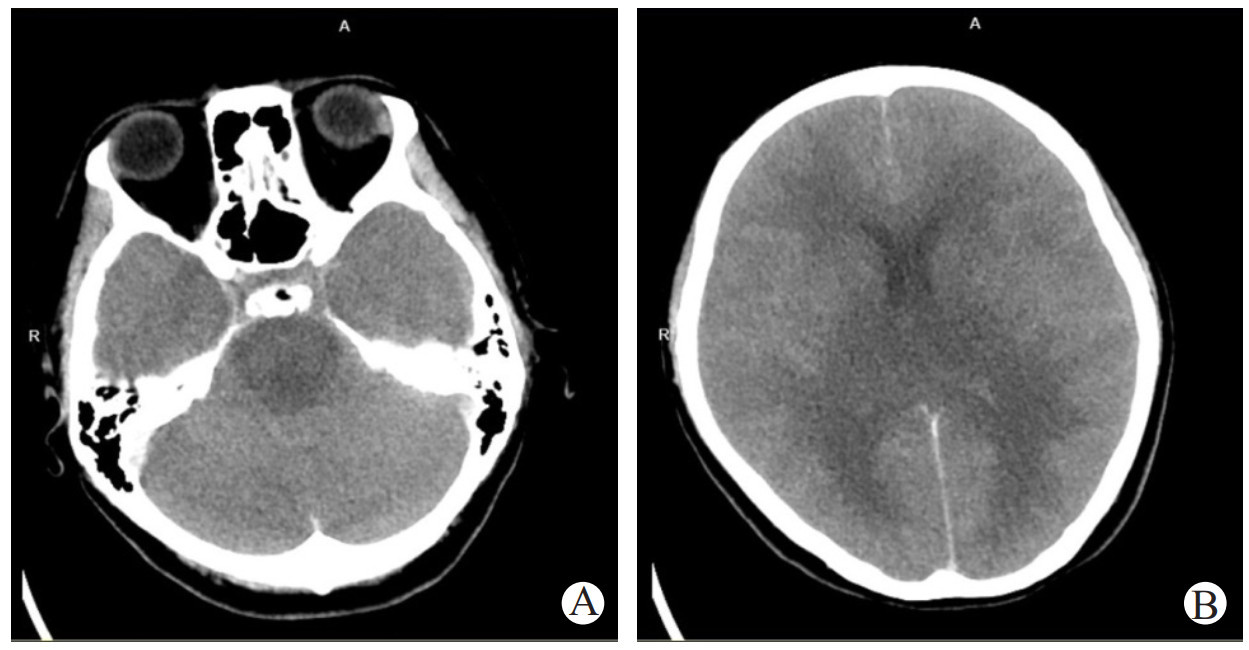

3月22日6:00护士巡视病房呼叫患者,患者再次出现呼之不应、意识模糊,GCS评分E2V1M5=8分,神经系统查体提示双侧巴氏征阳性。予加急颅脑MRI检查提示(见图 2):两侧额叶皮层下、半卵圆中心、侧脑室旁、背侧丘脑、两侧小脑半球、脑干见多发斑片状稍长T1长T2信号,DWI呈高、等信号,于FLAIR上呈高信号,表现为“同心环”样改变,中心低信号,周围环绕着高信号。其中两侧背侧丘脑肿胀明显,三脑室受压。

注:A为该患者颅脑MRI的T1加权图像,B为T2加权图像,C为弥散加权图像(DWI),D为液体衰减反转恢复序列图像(FLAIR);两侧额叶皮层下、半卵圆中心、侧脑室旁、背侧丘脑、两侧小脑半球、脑干见多发斑片状稍长T1(A)长T2信号(B),DWI呈高、等信号(C),于FLAIR上呈高信号(D),表现为“同心环”样改变,中心低信号,周围环绕着高信号,其中两侧背侧丘脑肿胀明显,三脑室受压 图 2 3月22日患者颅脑MRI和DWI检查

本案例为青年女性患者,发病前有呼吸道感染症状、发热,起病急,神经系统体征为双侧巴氏征阳性,症状表现为意识障碍、继发性癫痫、转氨酶快速升高,脑脊液检查提示蛋白水平升高,有核细胞计数无明显变化。头颅MRI提示两侧额叶皮层下、半卵圆中心、侧脑室旁、背侧丘脑、两侧小脑半球、脑干不同程度受累。符合ANE的诊断标准。